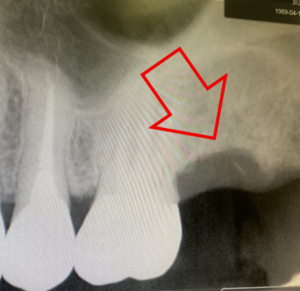

こちらが治療前のレントゲン写真です。丸を付けた箇所がインプラント治療を受ける場所です。

左の赤丸は、虫歯の為、歯の根っこが悪くなり抜歯が必要な場所です。(右上4番)

①虫歯の為抜歯が必要であった歯(右上の前から4番目の歯)の抜歯を行い(上の写真)